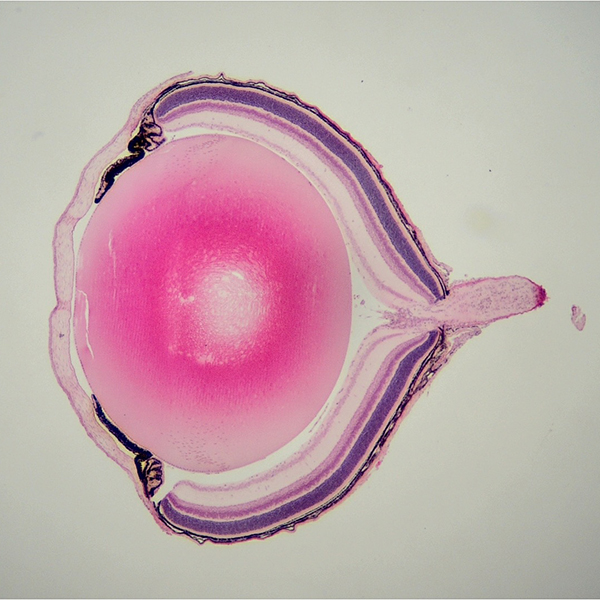

Prof. Xiong earned her PhD in Biomedical Sciences from the University of Chicago in 2010, where she worked under the guidance of Prof. Ilaria Rebay to investigate the spatiotemporal coordination of signaling pathways during Drosophila compound eye development. In 2011, she joined Prof. Constance Cepko’s lab at Harvard Medical School for postdoctoral research training, focusing on the mechanisms of inherited blindness and developing gene therapies to preserve vision in preclinical models. She established her independent research group at the City University of Hong Kong in 2015 as an Assistant Professor and was promoted to Associate Professor in 2021.

Vision is our most critical sense, enabling perception of the world through photoreceptors-specialized retinal neurons that convert light into neural signals. However, these cells are highly susceptible to degeneration in diseases such as Retinitis Pigmentosa, which is a severe inherited disorder, and Age-related Macular Degeneration, the leading cause of blindness in the elderly. Our lab seeks to decipher molecular mechanisms that enable photoreceptor rescue, replacement, or regeneration in degenerative conditions. We aim to translate discoveries from animal models into gene and regenerative therapies for patients.

• Gene Therapy Development – Designing adeno-associated virus (AAV)- and lipid-nanoparticle (LNP)-based gene therapy, gene editing, and regenerative therapy for retinal degenerative diseases.

• High Myopia Research – Investigating disease mechanisms and therapeutic interventions for myopia.